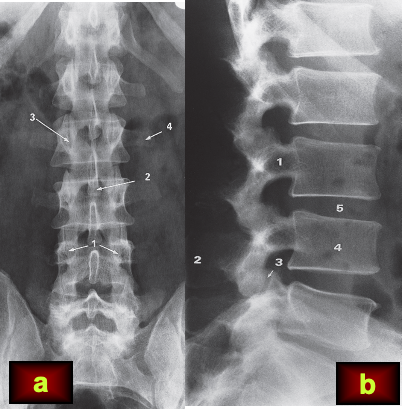

1, pedicles; 2, spinous process; 3, facet joint; 4, transverse process.

(b) Lateral view. 1, pedicles; 2, spinous process; 3, facet joint; 4, vertebral body; 5, disc space.

Note how the height of the disc spaces increases from L1 to L5 with the exception of the L5/S1 disc space which is normally narrower than the one above.